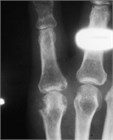

急性の痛風は結晶沈着によって引き起こされる痛みを伴う関節炎である.一般的に40~60代で罹患する.どの関節にも発症しえるが,古典的には第1趾の中足趾節間(MTP)関節炎として描写される(足部痛風”Podagra”).鑑別疾患には化膿性関節炎があり,初回発作時やred flag sign(発熱等)がある場合は関節穿刺が必要となる場合がある.鎮痛薬の選択肢としては,NSAIDsやコルチコステロイド(経口または筋注のいずれか),コルヒチン,重症例では麻薬性鎮痛薬でさえ挙げられる.繰り返す発作に対しては,尿酸を減少させる生活習慣の改善や薬物療法を考慮すべきである.